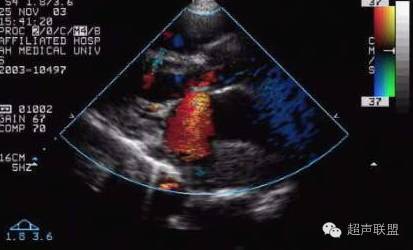

超声多普勒:脉冲多普勒(PW)的频谱轮廓异常

正常的双峰消失、内部充填,连续多普勒(CW)测通过瓣口血流速度增快,超声多普勒血流显像技术(CDFI)可直接显示瓣口多色镶嵌的射流束,其起点宽度与瓣口的直径相关,是最简便易行的瓣口面积半定量法。

脉冲多普勒超声心动图检查时,将取样容积置于左室流入道口或左房侧,见舒张期e 、a 两峰消失,频谱展宽呈宽带曲线。二尖瓣狭窄舒张期血流彩色多普勒于二尖瓣口左室侧可见彩色镶嵌样血流信号,流束变细,流速增快,血流颜色明亮而鲜艳。

二尖瓣狭窄并关闭不全♦ 合并关闭不全时收缩期在左房侧可见彩色镶嵌的二尖瓣口返流信号